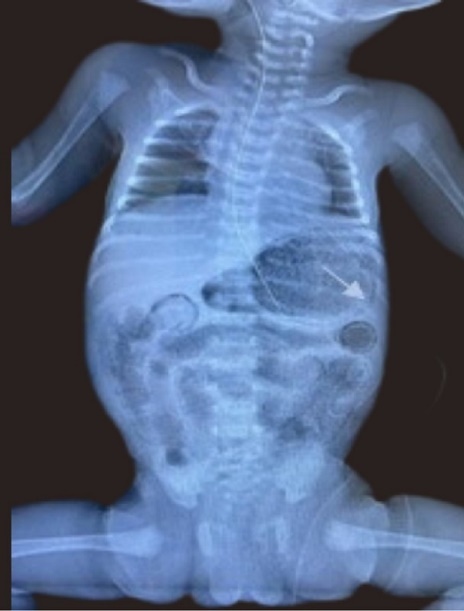

A late preterm (34+2) female infant, twin 2 of a diamniotic dichorionic gestation was delivered to a 23 year old multiparous female with minimal antenatal care, and unremarkable booking parameters. She presented with PPPROM with breech presentation and received 1 dose of dexamethasone and 2 doses of Ampicillin, one of which was administered during the intrapartum period. The baby was delivered via SVD and was suctioned and stimulated at birth. She had a birth weight of 2.11 kg. APGARs were 8 and 9 at 1 and 5 minutes respectively. Subsequent to essential newborn care, she was admitted to the NICU, screened to include blood and urine culture, complete blood count (CBC), and CXRAY and commenced on first line antibiotics. Feeds were commenced at target for age using a cow’s milk protein based formula as breast milk was unavailable. By day three of life baby was noted to have temperature instability, poor feeding, with a markedly distended firm full abdomen, with visible bowel loops. Frank blood was also noted via the nasogastric tube; however she remained haemodynamically stable. She was therefore re-screened, stepped up to second line antibiotics and an urgent A-Xray was done as shown in Figure 3. This revealed gastric pneumatosis, which was promptly recognized given the recent ‘findings of the previous case’, and pneumatosis intestinalis of small bowel. Nil portal venous gas was seen. Thromocytopenia was also confirmed; with the lowest platelet count of 93 x 103/uL(x 109/L) being observed. She was transfused with whole blood as the hemoglobin dropped from 18.0 g/dL to 14.3 g/dL. She remained NPO and received triple therapy for 14 days. Thrombocytopenia resolved. All cultures done were sterile. She recommenced feeds on Day 18 of life, subsequent to a repeat A-XRAY which confirmed radiological resolution of NEC. She subsequently had an uncomplicated outcome and was notably thriving when reviewed one month post discharge.

Figure 3.Anterior posterior Chest and abdominal radiograph showing gastric pneumatosis (arrow shown) and pneumatosis intestinalis.